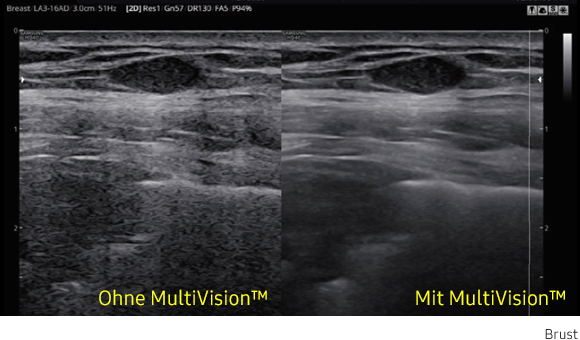

MultiVision

Durch elektronisches Beamsteering und die Nutzung vieler Scanlinien erzeugt MultiVision qualitativ hochwertige Ultraschallbilder. MultiVision bietet Ihnen eine bemerkenswerte räumliche und kontrastreiche Auflösung, mit weniger Artefakten als je zuvor.

Ultraschallbild Brust links ohne MultiVision und rechts mit MultiVision von Samsung. Ultraschallbild Brust links ohne MultiVision und rechts mit MultiVision von Samsung. Ultraschallbild Brust links ohne MultiVision und rechts mit MultiVision von Samsung. Ultraschallbild Brust links ohne MultiVision und rechts mit MultiVision von Samsung.